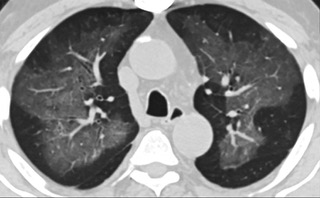

疑點一,電子煙患者的CT影像和臨床表現并不具有特異性。所謂美國電子肺炎患者,其實是對沒有其他合理診斷證據、吸食電子煙肺炎患者的統稱。這些患者在病發前90天內吸食了電子煙,尤其值得注意的是,部分患者的CT影像特征和臨床表現與病毒性肺炎患者極其相似。

中、下肺軸位CT平掃顯示毛玻璃樣混濁伴胸膜下保留。(同一病人CT影像)